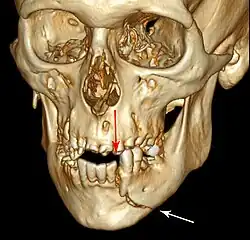

3D CT reconstruction of mandible fracture, white arrow marks fracture, red arrow marks moderate displacement and open bite -

Open reduction with direct skeletal fixation allows the bones to be directly mandibulated through an incision so that the fractured ends meet, then they can be secured together either rigidly (with screws or plates and screws) or non-rigidly (with transosseous wires). There are a multitude of various plate and screw combinations including compression plates, non-compression plates, lag-screws, mini-plates and biodegradable plates.

Rigid internal fixation of parasymphysis fracture of the mandible. White arrow marks fracture, black arrow marks arch bar on lower teeth -

Rigid internal fixation of right condyle fracture with mini-plate on the neck of the condyle. Black arrow marks right earlobe, white arrow marks head of the condyle -